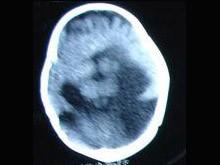

问题 9个月女婴,头颅迅速增大,四肢肌力下降,CT表现如图,首先考虑以下哪个疾病 ( )

选项 A、脑灰质异位 B、无脑回畸形 C、Dandy-Walker综合征 D、前脑无裂畸形 E、胼胝体发育不全

答案 D